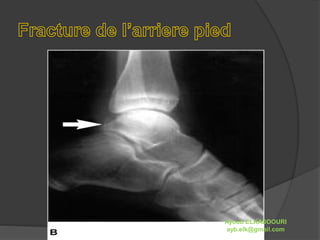

 Elle concerne surtout le calcanéum, très rarement

l’astragale. Ce sont des fractures qui surviennent à la

suite d’un impact très important. On les rencontre

surtout dans les chutes.

 Le diagnostic n’est pas évident lorsqu’il n’existe qu’un

trait de fracture sans déplacement. La

personne marche parfois correctement, aussi c’est la

notion de violence du choc qui doit faire songer à la

radio systématique.

 Sinon dans les fractures pluri-segmentaires nues, on

remarque un affaissement de la voûte plantaire et une

douleur à la mobilisation de l’arrière pied. Peu après

l’incident, apparaît bien souvent une ecchymose au

niveau du calcanéum.